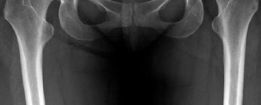

Radiographic assessment must be exhaustive. A standardized anteroposterior (AP) radiograph of the pelvis, centered over the symphysis pubis with neutral pelvic tilt and rotation, is mandatory. On this view, the LCEA, Tönnis roof inclination angle, and extrusion index are calculated. For instance, an LCEA of 18° and a roof inclination of 20° confirm severe lateral and superior uncoverage. A false profile view of the Lequesne and de Sèze is critical for assessing anterior coverage (anterior center-edge angle) and anterior joint space. Dunn 45° and 90° views, or a cross-table lateral, are utilized to evaluate the femoral head-neck junction for CAM morphology.

Advanced imaging is non-negotiable in the revision setting. A high-resolution MRI or MR arthrogram of the hip is required to assess the articular cartilage, the integrity of the ligamentum teres, and the state of the remaining labrum or capsular scar tissue. Anterolateral loss of joint cartilage is a frequent finding in dysplastic hips post-labral resection. Furthermore, a CT scan or MRI utilizing torsional sequences from the hip through the knee is essential to quantify femoral version. A measured femoral anteversion of 36° dictates that a derotational femoral osteotomy (DFO) must be incorporated into the surgical plan to restore normal biomechanics and prevent recurrent anterior subluxation post-operatively.